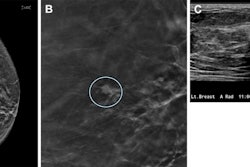

Reliable evidence about the long-term impact of digital breast tomosynthesis is in relatively short supply, so the publication of a study from the U.S. is bound to generate great interest.